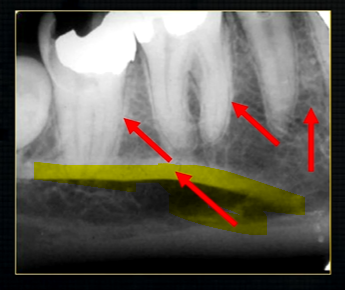

periapical radiograph → posterior maxilla

radiolucent maxillary sinus and radiopaque floor

radiopaque shadow cast by zygoma, hollowed out by maxillary sinus

lower end of the dense, zygomatic bone

posterior aspect of the maxilla - smooth round tuberosity

1st image taken using the bisected angle technique

2nd was taken using the geometrically accurate, paralleling technique

upper image is geometrically distorted

shadow caused by zygoma

this was taken using the bisected angle technique

x ray beam was directed below the zygoma

very lower of the zygoma is seen - projected above the apices